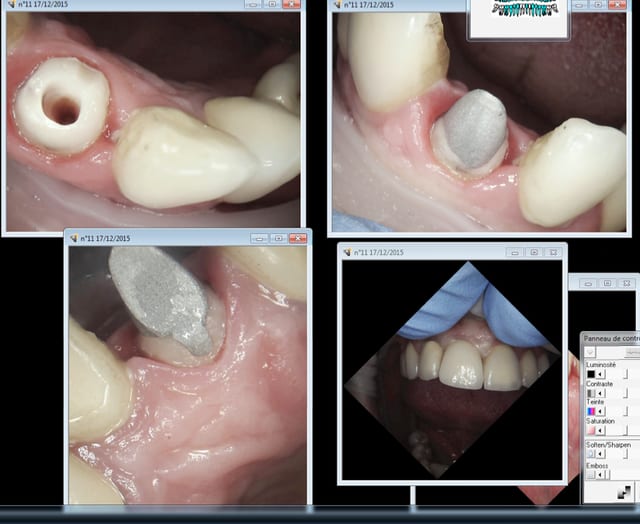

> toutefois regardes un peu :

> la photo 1 :resultat a 4 ans d'un bridge sur inlay core en 1 fois .

> la photo 2 avec de vrais inlays cores

>

> alors expliques moi , comment je peux les facturer 183 e ?

> quelque chose me dit que le resultat sera meilleur , non ?

Tu as raison enlaye il faut poser les ic-coiffes en 2 temps.

1 tu scelles l'inlay core.

2 tu scelles la couronne.

Et pas l'inverse ! -))))